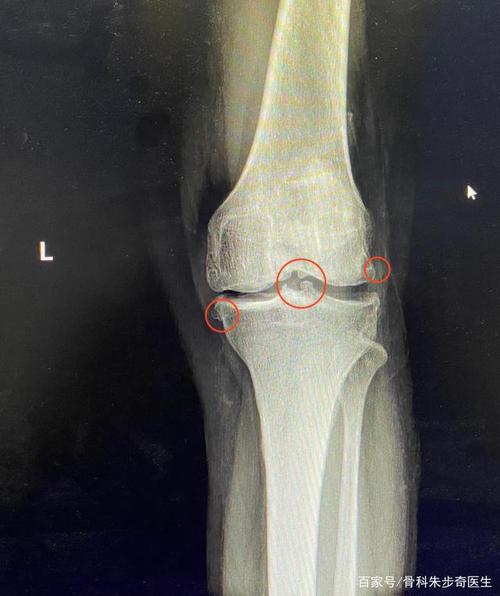

辟谣!膝关节长大量骨刺可以不手术,磨掉骨刺就能止痛并改善活动

ct提示双膝关节退变,双侧胫腓骨局部骨皮质增厚并条索状突起,骨刺增粗

膝盖长骨刺

膝关节骨质增生图片